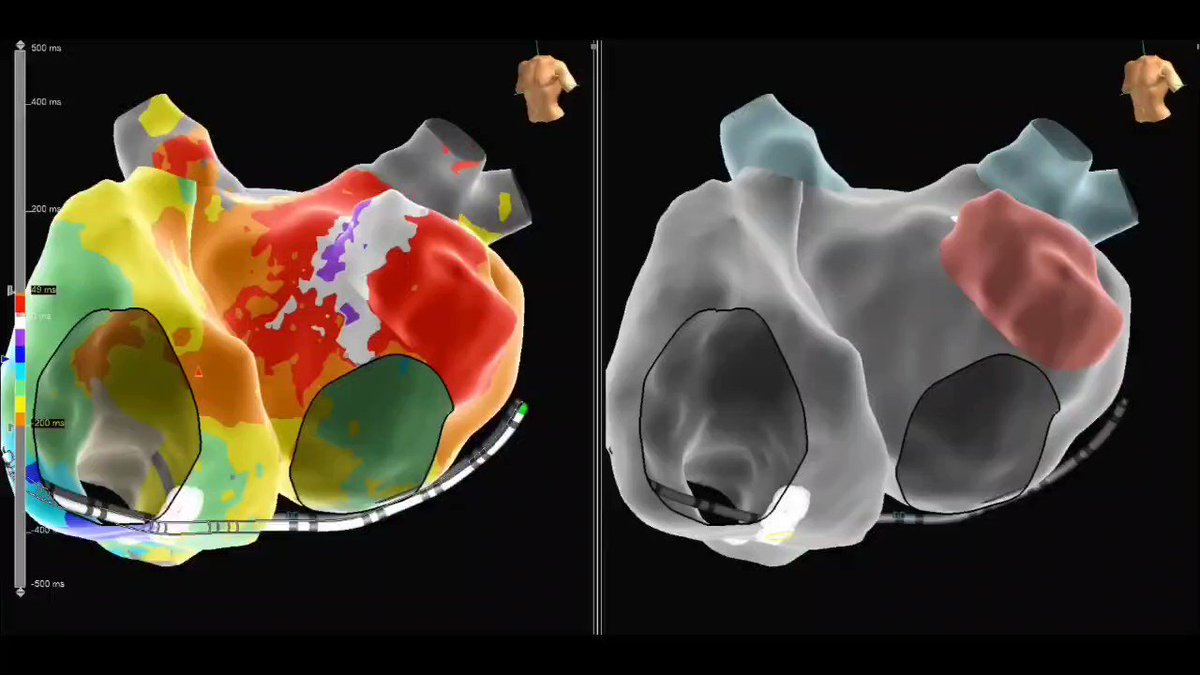

Micro-reentrant AT Mondays?!? Let's go! 🎯 Entire re-entrant circuit on the Grid EGMs imperceptible on recording system <0.06 mV Annotated automatically based on frequency w #OTNF One burn term 🔥🔥#MapMoreBurnLess @AbbottCardio

Entire re-entrant circuit on the Grid

EGMs imperceptible on recording system &amp;lt;0.06 mV

Annotated automatically based on frequency w #OTNF

One burn term 🔥🔥#MapMoreBurnLess